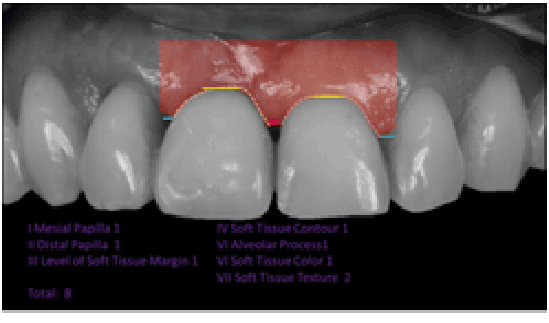

PES的初步评估(图2)显示为8,WES为6(图3)。这种类型的诊断在治疗前使用具有很大的价值,因为它提供了足够的信息来计划牙周手术,并取得更好的美学结果。PES/WES评估所获得的价值代表了部分受损的美学条件。PES≤7 / WES≤5为美学损害的临床病例;另一方面,PES≥12 / WES≥9表示高度适宜的美学价值或几乎完美的康复[9,10]。由于单独的WES不足以规划最终的康复,这是由DSD[8]的一些步骤来补充的。图4显示了康复数字化规划的各个阶段。在拍摄诊断图片(a)后,画一条平行于双瞳孔平面的线(B-蓝线)以及牙齿和牙龈的轮廓。这些参考线分别被转移到一个单色背景中,以突出牙齿之间的差异(C)。牙齿牙龈差异诊断后,将矫正平面投影到差异最大的一侧。因此,根据对侧对称的牙龈高度(D),在第11和12颗牙齿上设计了一条红色虚线。从第21颗牙齿到第11颗牙齿也做了同样的投影。在重叠的镜面轮廓中,可以看到11略大于21的宽度。 In addition, it can also be noticed that the height of the 11 is larger than that of its counterpart.

图2:粉色美学评分为插图案例